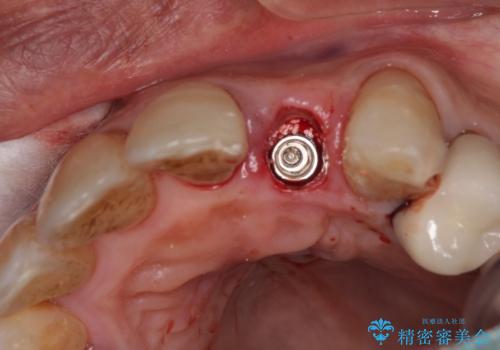

抜歯、インプラント埋入、仮歯の装着が同時に可能な1DAYインプラントが適用可能と判断されたため、インプラントによる補綴治療を行うこととしました。

前歯のインプラント治療は、従来の抜歯から数ヶ月待機する手法では、骨造成や歯肉移植など付随の処置が多く必要となり、費用、期間、身体的負担のいずれもが多大となります。

抜歯時にインプラントを埋入することでそれらの負担を大きく軽減させることが可能です。